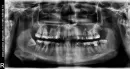

Готовлюсь ставить брекеты. Нужно удалить все зубы мудрости. Верхние удалила месяц назад. Осталось удалить 2 нижних зуба мудрости и вылечить 5 зубов. Врач посоветовал поменять пломбы перед брекетами на нижних 7-ках и на 3-х зубах наверху.

Скажите, пожалуйста, в каком порядке лучше делать? Сначала залечить зубы, а потом вырывать восьмерки? Или сначала вырвать, а потом лечить? Или без разницы?